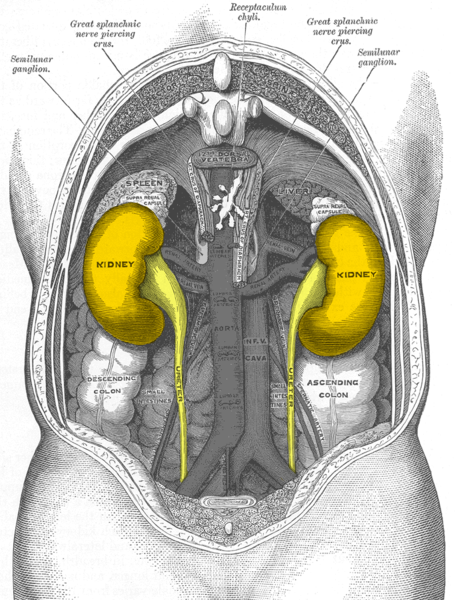

Abb. 1: Lage der Nieren (Ansicht von Körperrückseite!

Bildquelle: Gray1120-urinary-tract von Roxbury-de [public domain], via Wikimedia Commons

Benenne Nieren und Nebennieren am Torso. Beschreibe deren anatomische Lage.

Nieren und Nebennieren liegen im hinteren Oberbauch, d. h. hinter Magen, Darm, Bauchspeicheldrüse und Leber, leicht nach unten versetzt rechts und links der Wirbelsäule.-